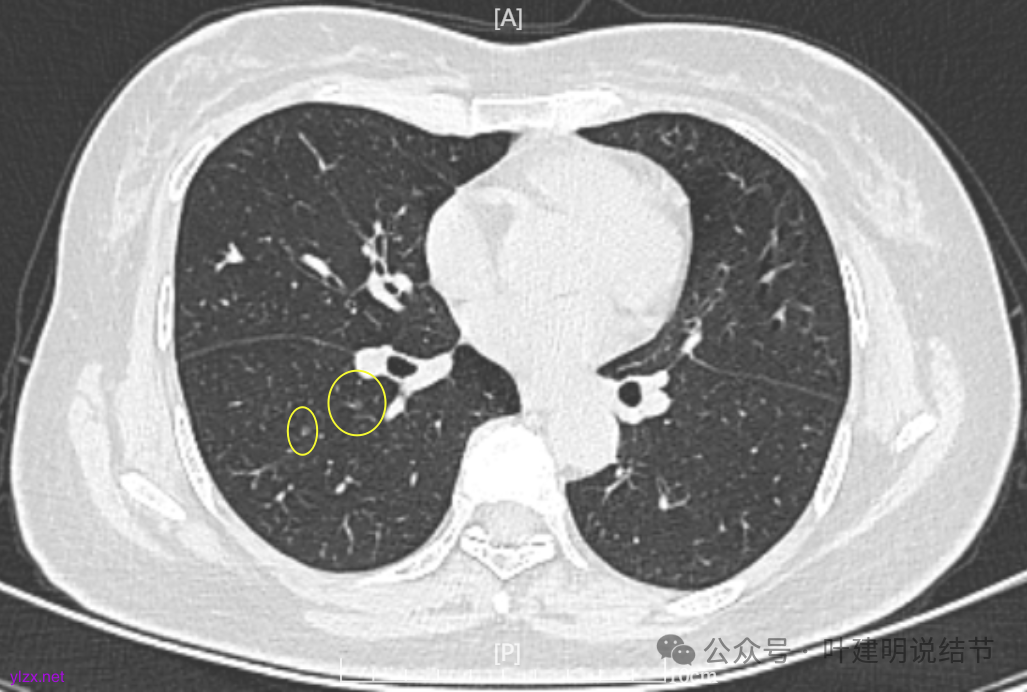

1.2021年12月因感冒咳嗽做了胸部CT,显示多发结节。有大的0.7*0.5cm。

2.2022年5月2日复查增强CT,显示肺结节0.7*0.6cm

4.2022年7月31日做了ct复查,报告显示结节增大,0.8*0.7cm。

病灶7:右下叶胸膜下淡而微小的磨玻璃结节,考虑肺泡上皮增生可能性大。